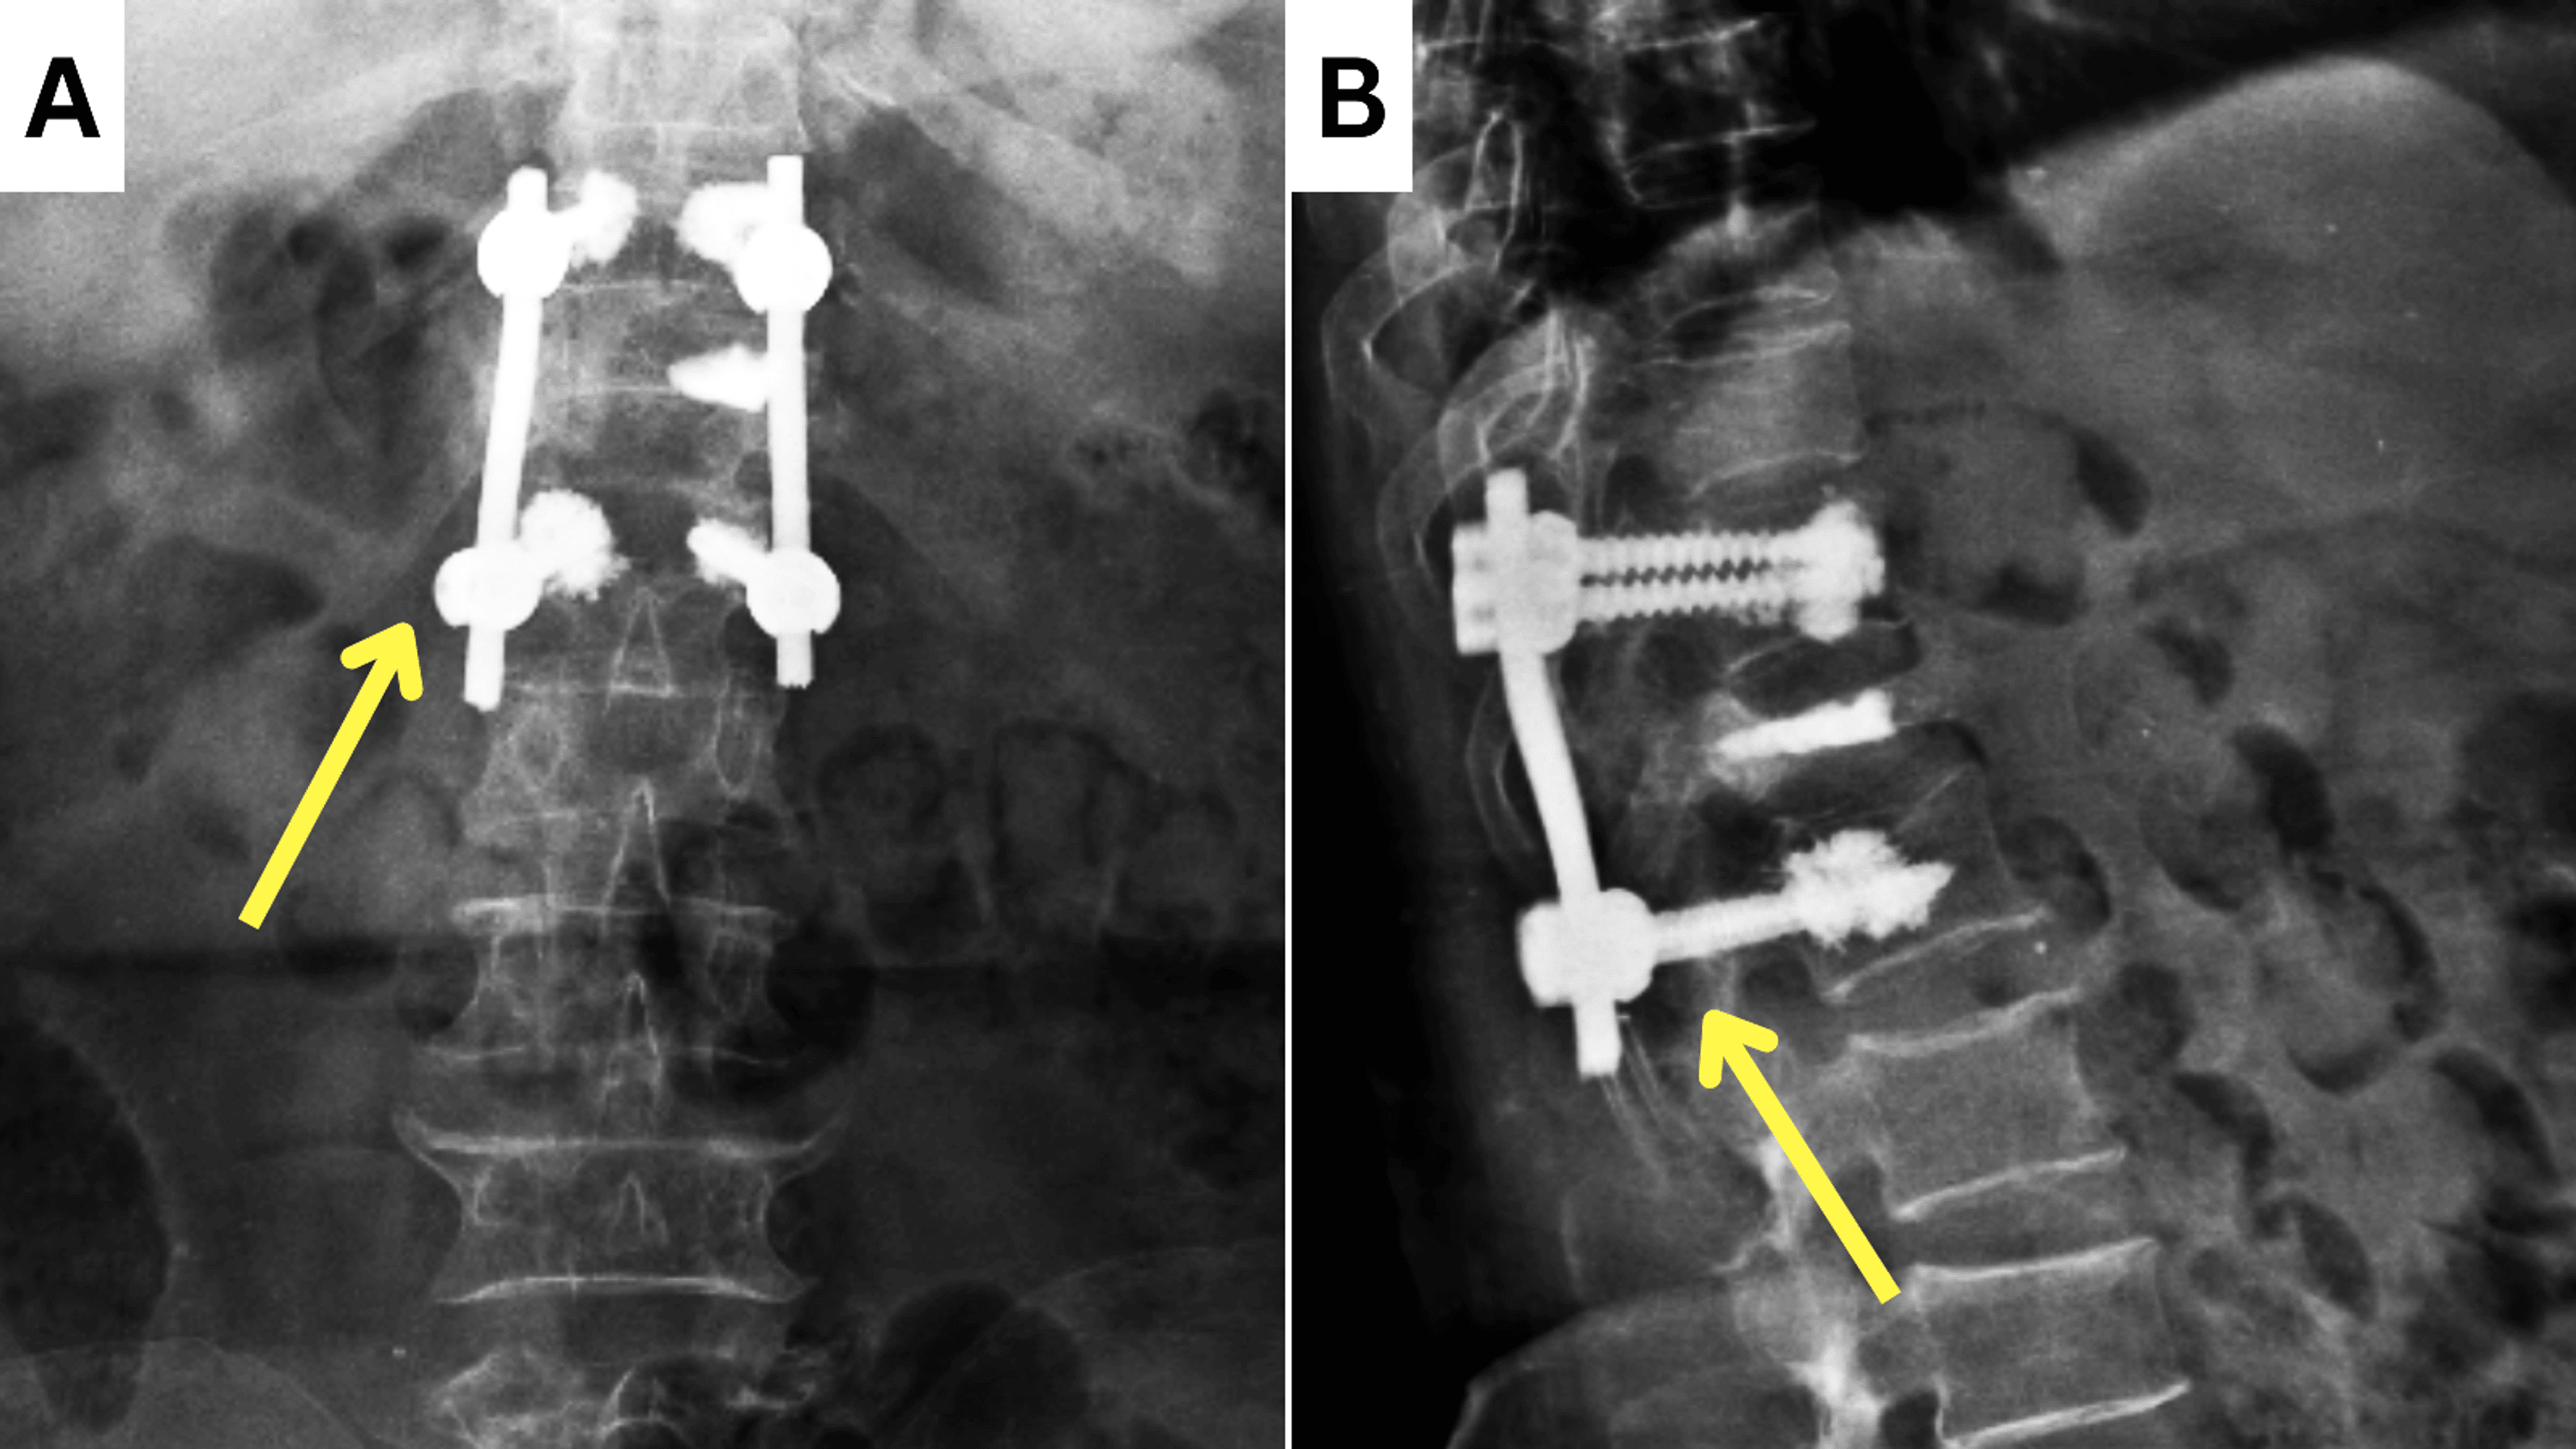

Fig5ac Anteroposterior and lateral radiograph of thoracolumbar spine Compression Fracture D12 compression fractures affect many patients worldwide and are most common in elderly populations, especially postmenopausal. pain from a spinal compression fracture allowed to heal naturally can last as long as three months. osteoporotic vertebral compression fractures are very common fragility fractures of the spine that affect up to 50%. compression fractures can result from osteoporosis, trauma. Compression Fracture D12.

Thoracolumbar fractureD12 burst fracture posterior Compression Fracture D12 pain from a spinal compression fracture allowed to heal naturally can last as long as three months. osteoporotic vertebral compression fractures are very common fragility fractures of the spine that affect up to 50%. vertebral compression fractures (vcfs) of the spinal column occur secondary to an axial/compressive (and to a lesser extent, flexion). compression fractures can. Compression Fracture D12.

D12 burst fracture with instrumentation YouTube Compression Fracture D12 compression fractures can result from osteoporosis, trauma or represent a pathological fracture secondary to another process (e.g. osteoporotic vertebral compression fractures are very common fragility fractures of the spine that affect up to 50%. vertebral compression fractures (vcfs) are the most common complication of osteoporosis, affecting more than 700,000 americans. compression fractures affect many patients worldwide. Compression Fracture D12.

3 years back operated case of d12 wedge compression fracture. Showing Compression Fracture D12 osteoporotic vertebral compression fractures are very common fragility fractures of the spine that affect up to 50%. vertebral compression fractures (vcfs) are the most common complication of osteoporosis, affecting more than 700,000 americans. compression fractures affect many patients worldwide and are most common in elderly populations, especially postmenopausal. compression fractures can result from osteoporosis, trauma or. Compression Fracture D12.